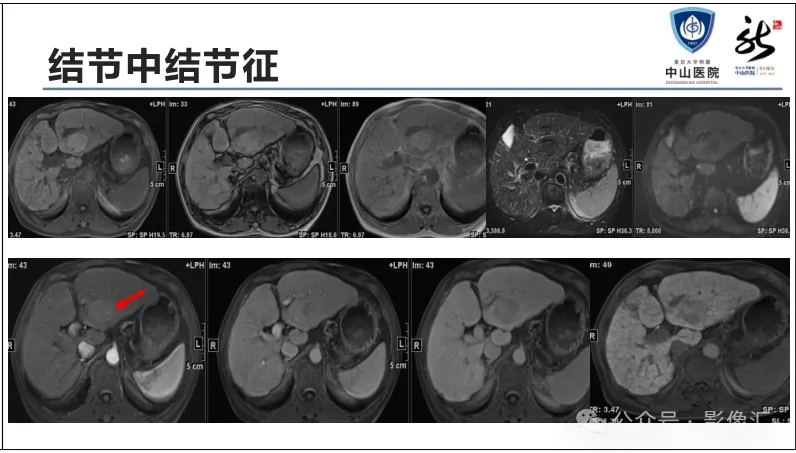

肝胆特异性对比剂增强肝胆图像判读方法与策略,课件来源于网络,作者复旦大学附属中山医院放射科饶圣祥教授。